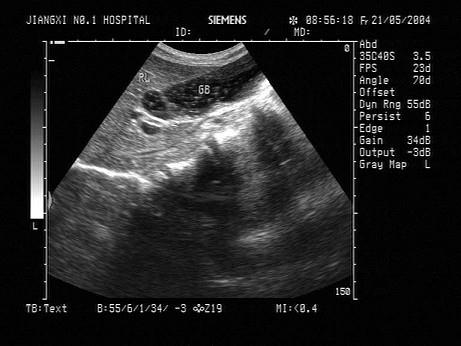

问题 女,25岁,因急性胰腺炎禁食5天。声像图如图所示。结合超声声像图,诊断为?(?)

选项 A.胆囊泥沙样结石 B.胆囊内胆汁淤积 C.胆囊多发性息肉 D.胆囊多发性胆固醇结晶 E.胆囊癌

答案 B